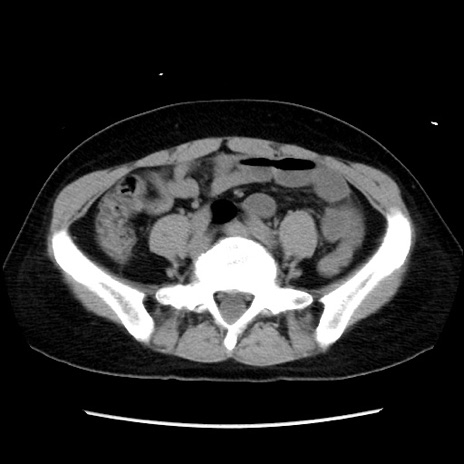

症例10(横断像)

【症例】 50歳代女性

【主訴】 腹痛

【現病歴】前日生レバーを食べた。今朝に排便あり。 昼前に突然発症の腹痛を生じ、当院救急外来を受診した。

【身体所見】 意識清明、腹部:平坦、軟、下腹部やや左を中心に圧痛・反跳痛あり、筋性防御あり